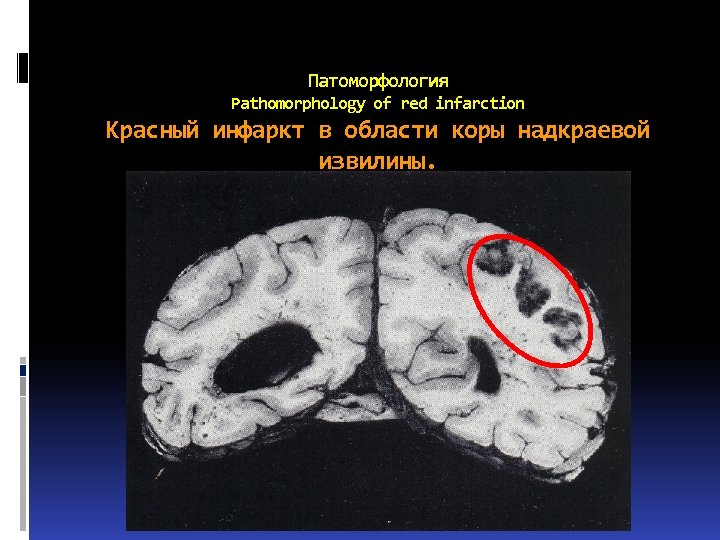

Красные инфаркты (составляют 1 -5%) бывают обычно небольших размеров, развиваются только в сером веществе мозга, чаще всего в коре, реже – в подкорковых узлах. В белом веществе они не встречаются. Red infarctions consist 1 -5% of all

Красные инфаркты (составляют 1 -5%) бывают обычно небольших размеров, развиваются только в сером веществе мозга, чаще всего в коре, реже – в подкорковых узлах. В белом веществе они не встречаются. Red infarctions consist 1 -5% of all

Развитию красного инфаркта всегда предшествует ишемия, затем присоединяется кровоизлияние в ишемизированную ткань.

Развитию красного инфаркта всегда предшествует ишемия, затем присоединяется кровоизлияние в ишемизированную ткань.

Патоморфология Pathomorphology of red infarction Красный инфаркт в области коры надкраевой извилины.

Патоморфология Pathomorphology of red infarction Красный инфаркт в области коры надкраевой извилины.